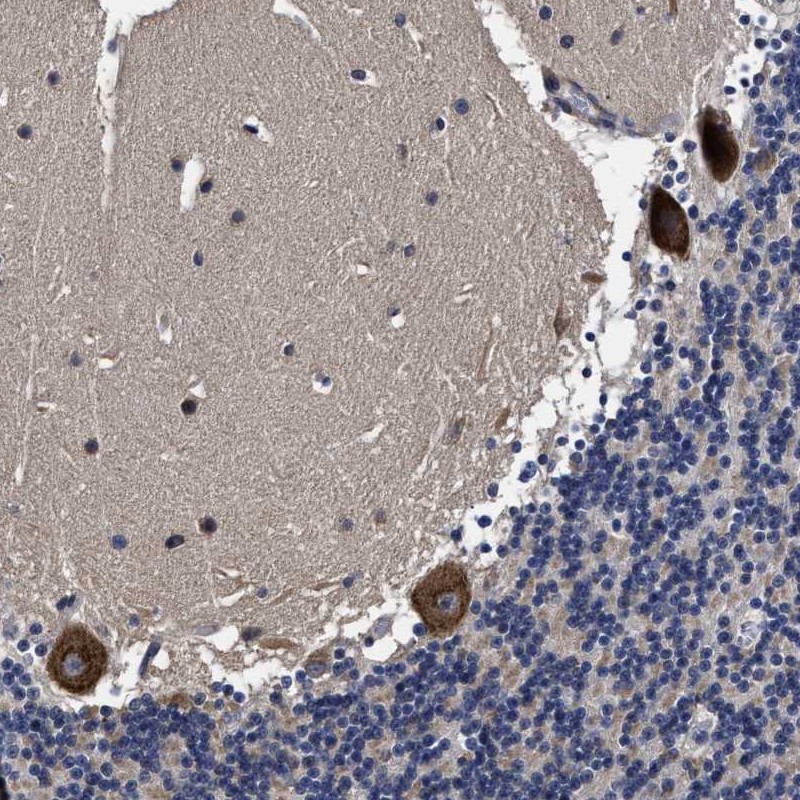

Immunohistochemical staining of human cerebellum shows strong cytoplasmic positivity in purkinje cells.